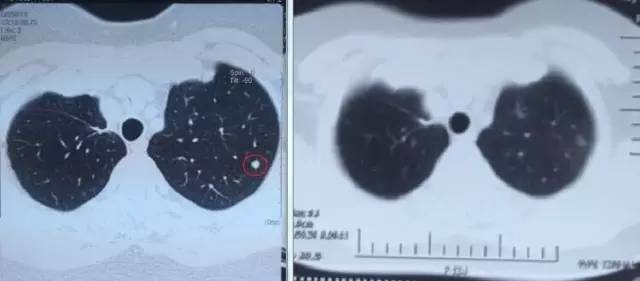

左图红色圈内是A45治疗前三个肺癌病灶,右图为治疗后病灶消失